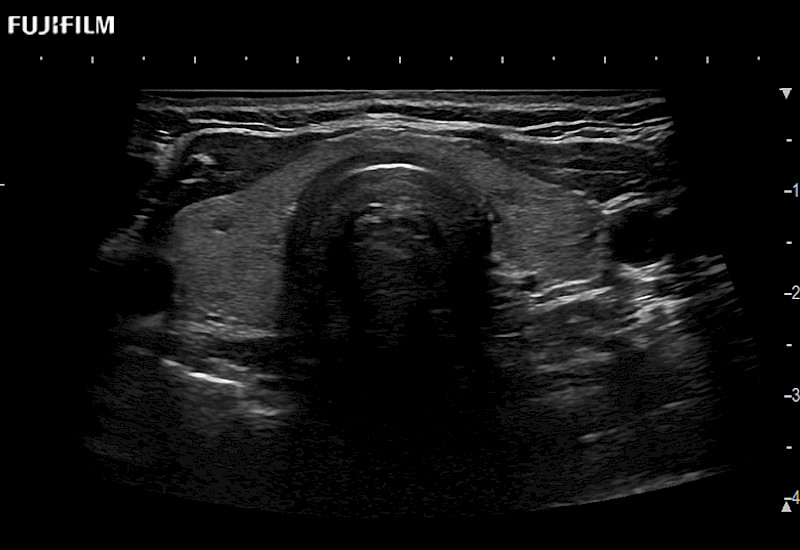

Learn moreFujifilm Healthcare continues to listen to the experts, our neurosurgeons, by developing an ultrasound system specifically designed for the Operating Room.

Guidance is the fundamental purpose for all of our surgical ultrasound technology. Fujifilm Healthcare is committed to designing tools that help neurosurgeons navigate inside the human body and provide the necessary information to immediately make critical surgical decisions.

With the ARIETTA Precision the next level of surgical ultrasound is here.